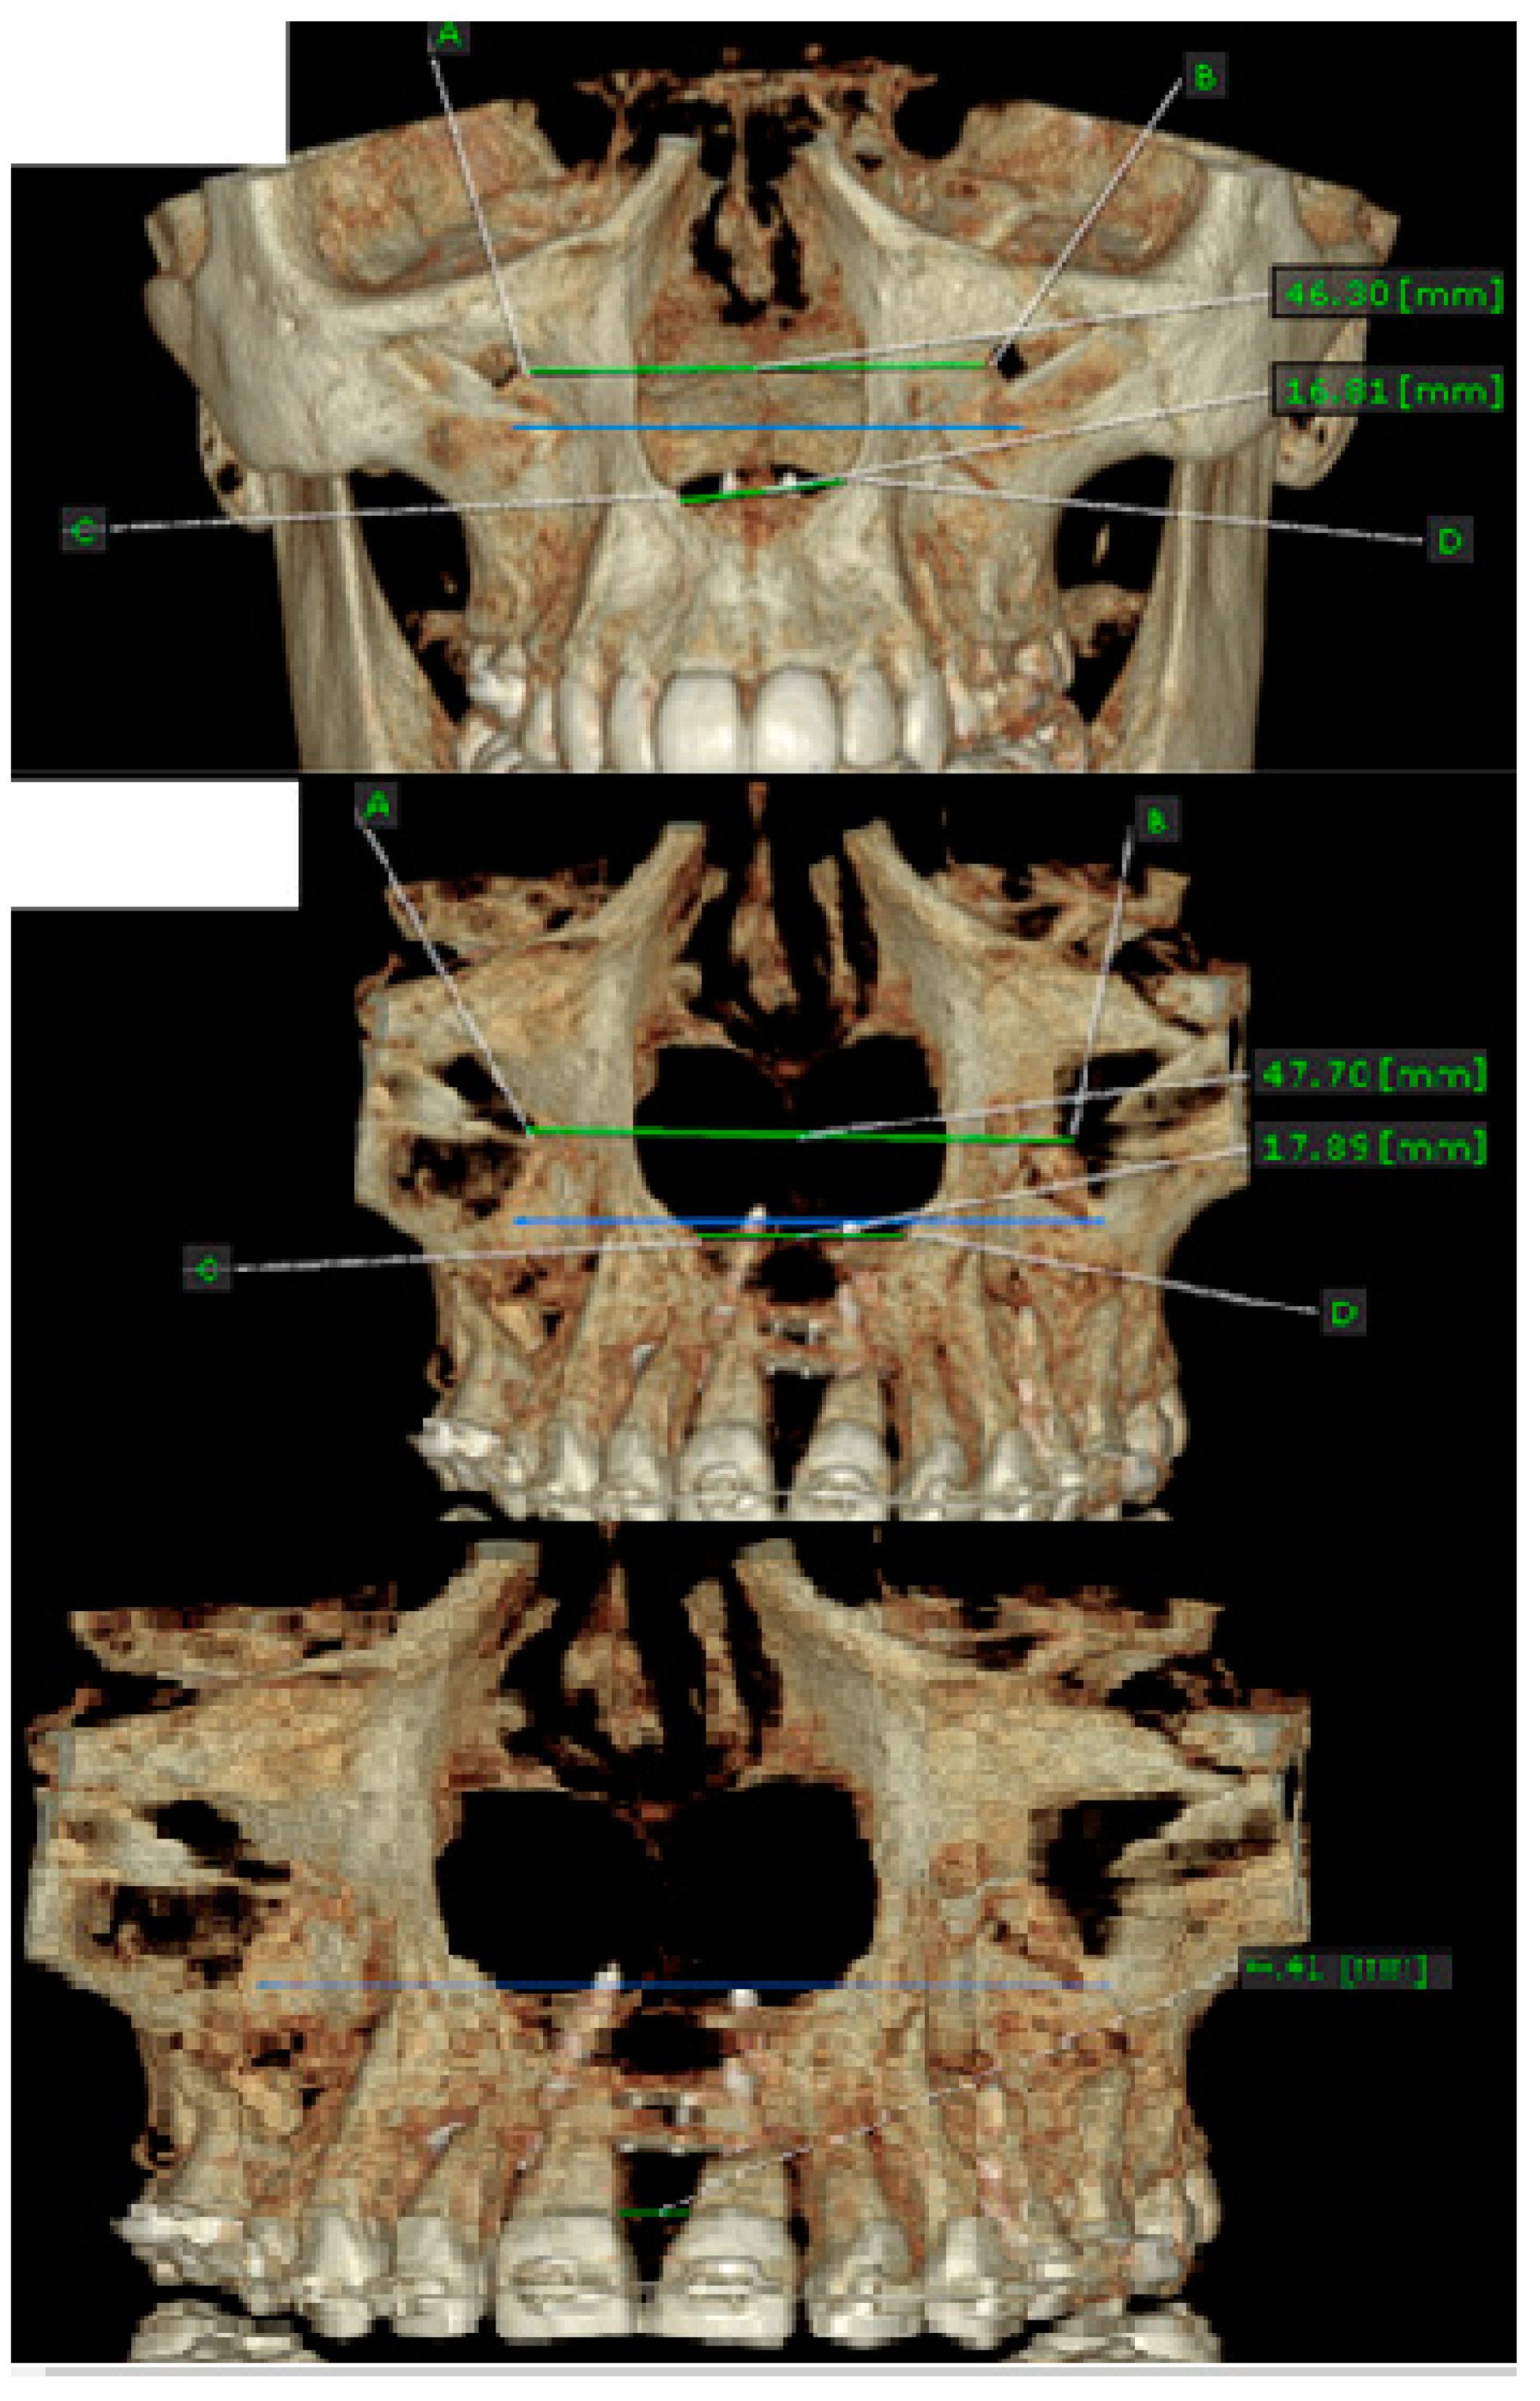

- MARPE associated with cortico-puncture therapy efficiently split the midpalatal suture in adults. The mean split at the anterior nasal spine (ANS) and posterior nasal spine (PNS) was 3.76 and 3.12 mm, respectively. The magnitude of the split at the PNS was smaller than at the ANS (by approximately 85% of the distance), showing that the opening of the midpalatal suture was almost parallel in the anteroposterior direction.

- MARPE therapy associated with cortico-puncture therapy had a positive outcome on midpalatal suture opening and maxillary advancement, but a medium molar inclination of 2.005° was also observed, suggesting that tooth movement cannot be avoided because of the anchorage of the MARPE device at the molar level.

| Mean | 3.766 | 3.125 |

| Mean | 87.88 | 85.87 |

| How big is the difference | −2.005 |